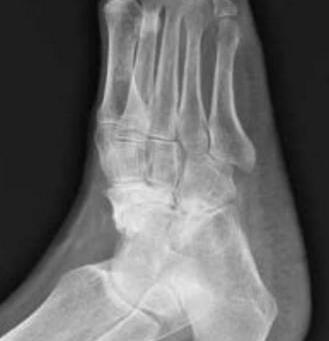

对于骨坏死诊断并不困难,患者几乎都是出现临床症状后就医,此时已属骨坏死中晚期阶段,X线片上常表现为:股骨正位片示关节软骨下骨骨质不均,可见斑片状影,呈不规则的斑片状,晚期可见骨质增生,关节间隙变窄,呈骨性关节炎变现。>>>将病症描述给医生,让医生帮您诊断